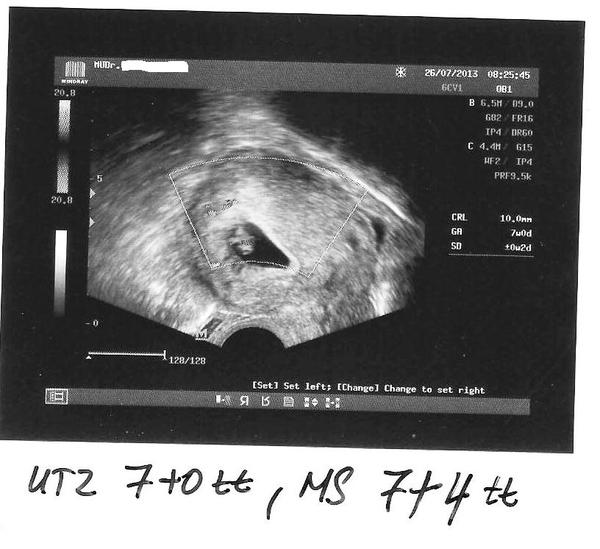

Dievcata hlasim ze som dnes testla 6DPO a su tam dve // Tesiim🙂🙂🙂🙂🙂🙂🙂dalsi testik v nedelu🙂🙂🙂🙂

@svetlanab neboj,bude to dobre...aj ja som stresmenka🙂🙂 a kedy ides na krvicku? Kedy si mala vklad? Ja 27.7.